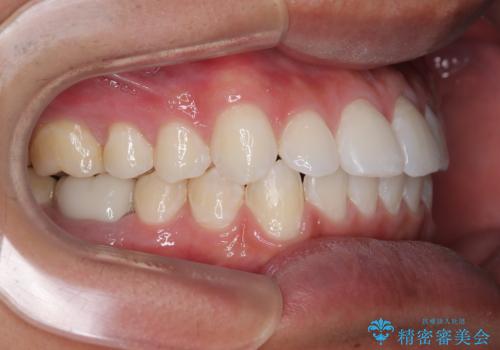

ワイヤー装置でもマウスピースでも対応可能でしたが、自己管理の煩わしさを気にされ、ワイヤー装置にて矯正治療を行うこととしました。

矯正治療後は、奥歯の銀歯をセラミッククラウンにて補綴治療を行うこととしました。

あっという間に歯列が整い、目立っていた銀歯もなくなり、清潔感のある口元になりました。